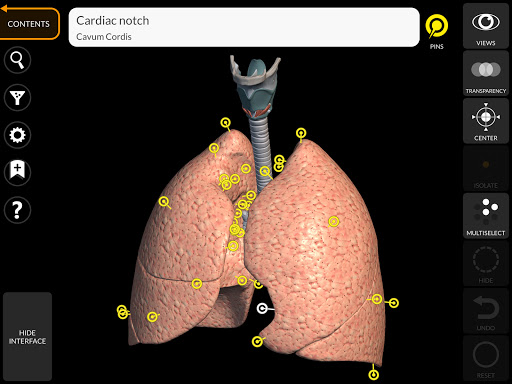

"Anatomy 3D Atlas" memungkinkan Anda mempelajari anatomi manusia dengan cara yang mudah dan interaktif.

Melalui antarmuka yang sederhana dan intuitif, Anda dapat mengamati setiap struktur anatomi dari sudut mana pun.

Model 3D anatomi sangat terperinci dan memiliki tekstur hingga resolusi 4k.

Pembagian berdasarkan wilayah dan tampilan yang telah ditetapkan sebelumnya memudahkan pengamatan dan studi bagian tunggal atau kelompok sistem dan hubungan antara organ yang berbeda.

saraf • Sistem pernapasan • Sistem pencernaan • Sistem urogenital (pria dan wanita) • Sistem endokrin • Sistem limfatik • Sistem mata dan telinga FITUR • Antarmuka yang sederhana dan intuitif • Putar dan perbesar setiap model dalam ruang 3D • Opsi untuk menyembunyikan atau mengisolasi satu atau beberapa model yang dipilih • Filter untuk menyembunyikan atau menampilkan setiap sistem • Fungsi pencarian untuk menemukan setiap bagian anatomi dengan mudah • Fungsi penanda untuk menyimpan tampilan khusus • Rotasi cerdas yang menggerakkan pusat rotasi secara otomatis • Fungsi transparansi • Visualisasi otot melalui tingkat lapisan dari yang superfisial hingga yang terdalam • Dengan memilih model atau pin, istilah anatomi terkait akan muncul • Deskripsi otot: asal, • Tampilkan/ Sembunyikan antarmuka UI (sangat berguna dengan layar kecil) MULTIBAHASA • Istilah anatomi dan antarmuka pengguna tersedia dalam 11 bahasa: Latin, Inggris, Prancis, Jerman, Italia, Portugis, Turki, Rusia, Spanyol, Mandarin, Jepang, dan Korea • Istilah anatomi dapat ditampilkan dalam dua bahasa secara bersamaan PERSYARATAN SISTEM • Android 8.0 atau yang lebih baru, perangkat dengan RAM minimal 3GB Reversi

• Sistem pernapasan